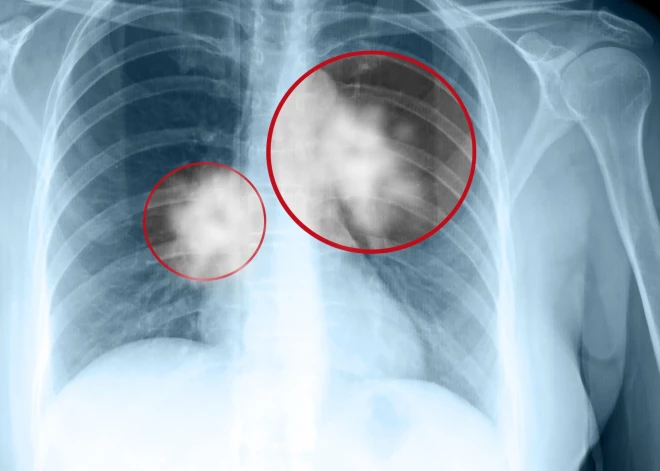

Plaušu vēzis ir stāvoklis, kad plaušās notiek patoloģiska vai neparasta šūnu augšana. Saskaņā ar PVO datiem plaušu vēzis veido aptuveni 13% no visiem vēža gadījumiem pasaulē. Tā kā plaušas ir cilvēka ķermeņa elpošanas mehānisma galvenais orgāns, daudzi domā, ka akūtas elpošanas problēmas vai sāpes ķermeņa augšdaļā ir vienīgās šīs slimības pazīmes. Tomēr tas tā nav.